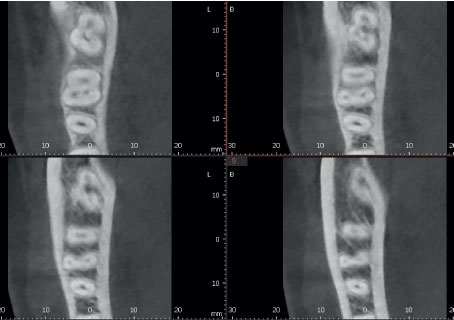

Режим Эндо с высочайшим разрешением

Режим Endo с объемом 4x4 см и размером вокселя 49,5 микрон оптимизирует обработку областей, представляющих повышенный интерес. Он идеально подходит для эндодонтии, поскольку стоматолог может получить изображение с высоким разрешением вокселей.

| ОБЫЧНЫЙ РЕЖИМ | ||||

|

||||

| ENDO РЕЖИМ | ||||